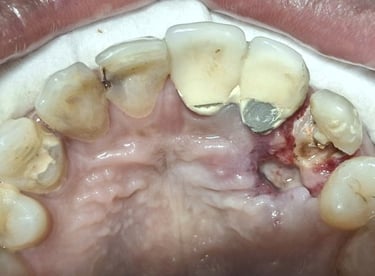

Tooth Colored Filling in Shyamal, Ahmedabad

Tooth-colored fillings are used to restore decayed or broken teeth while maintaining a natural appearance. These fillings blend seamlessly with your tooth color and help preserve your smile.

Before

After

All images shown here are real tooth colored filling cases treated at our clinic with patient consent.

At Shree Dental Care, cosmetic fillings are placed carefully with a focus on comfort, precision and long-term durability. We ensure minimal tooth cutting and natural-looking results.

If you are looking for aesthetic tooth colored filling in Shyamal, Ahmedabad, you can book an appointment with our clinic.